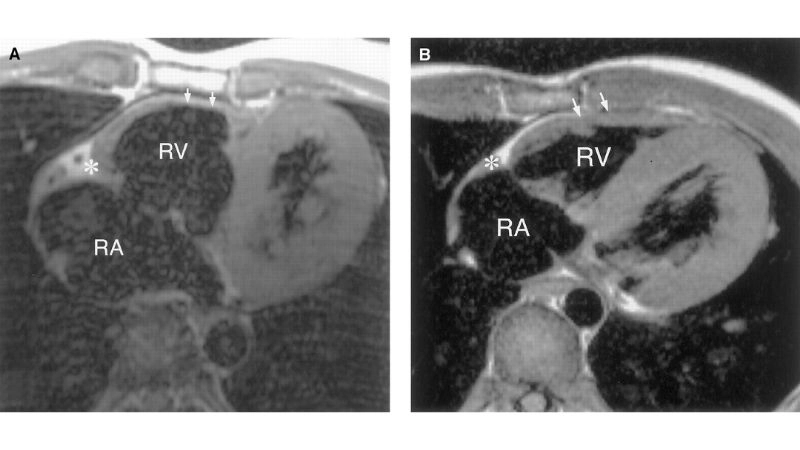

Images visual examples of Uhl's anomaly

Uhl’s anomaly is a rare congenital heart condition characterized by the near-complete absence of the right ventricular myocardium, resulting in a thin-walled and weakened heart chamber.